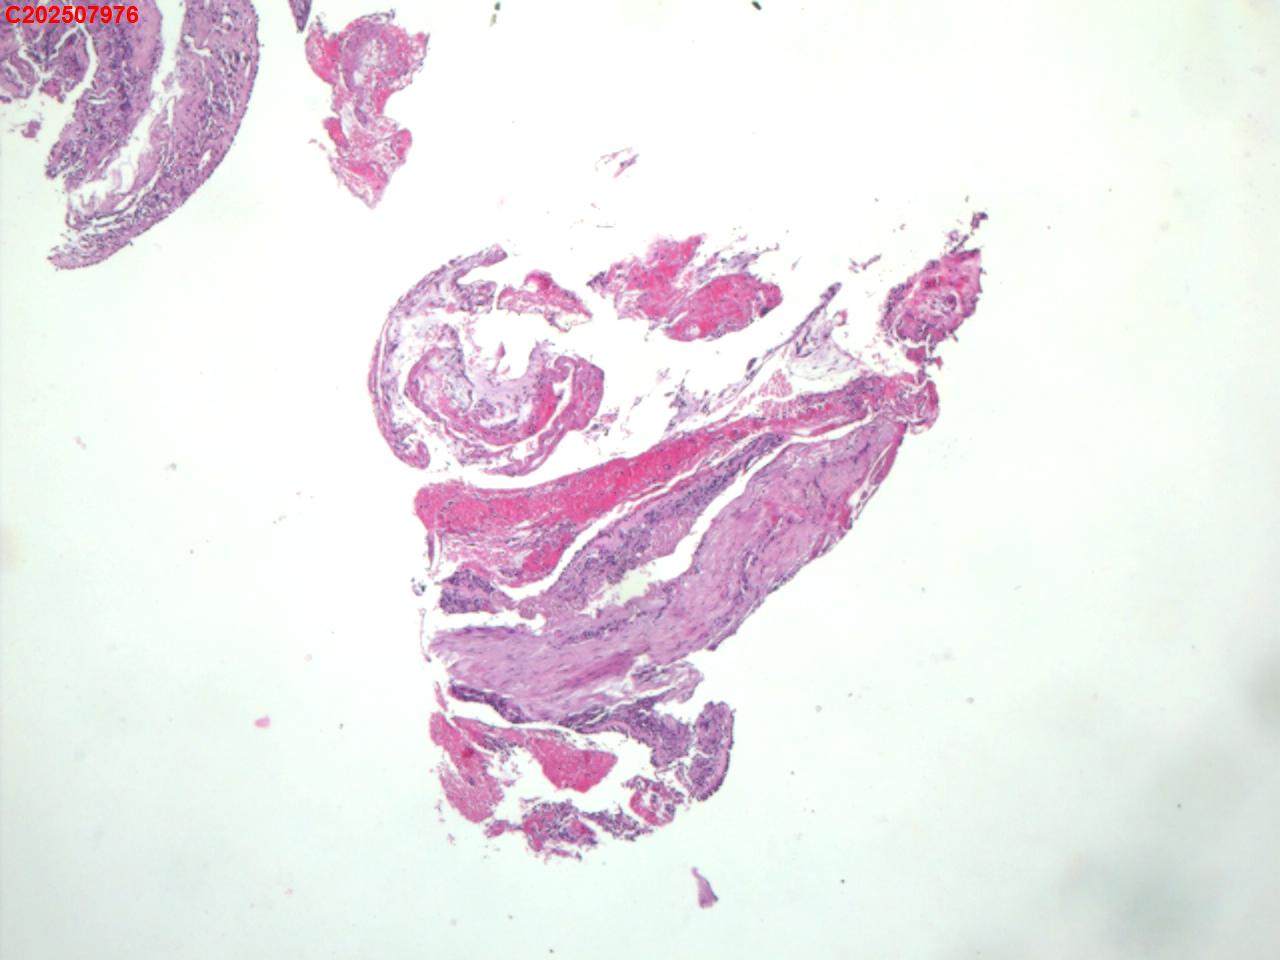

右肺上叶开口处 气管镜咬检

右肺上叶开口上缘处可见肉芽增生,予咬检。

图1

感觉:炎性纤维组织增生